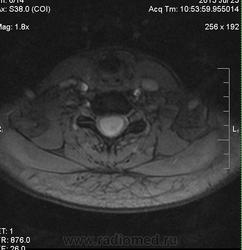

Сирингомиелия шейно-грудной локализации? Аномалия Арнольда-Киари I. Платибазия.

здоровенная сирингогидромиелитическая киста (по видимому, "высокого давления"), мальформация Киари 1.   также имеются признаки внутренней окклюзионной гидроцефалии.